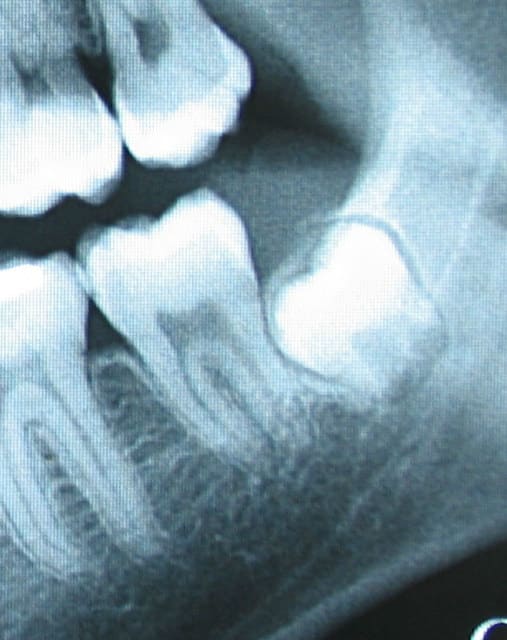

Voici une 48 et 38. Qu'est ce que tu en penses ? A laisser ou à extraire sachant qu'elles sont asymptomatiques chez une personne de 20 ans en bonne santé.

Pour tes radios, je laisserais en place.

pour canin

38 et 48 à laisser

La 38 a été extraite finalement. reste la 48.

J'avour que ce sont des extractions dites prophylactiques. On ne peut prévoir de façon absolue les complications sur ce genre de dents. Le seul truc sûr c que le contexte paro pour les 7 n'est pas idéal. De plus les extraire maintenant est beaucoup plus simple et moins risqué que dans 5 ans. Dans 5ans c sûr et certain que les racines seront de part et d'autre du nerf. J'avais quand même precrit un scanner pour info et sur la 48, les racines poussent effectivement sur le canal.

Le dernier argument c'est que le patient est jeune et qu'il va bien cicatriser avec le minimum de séquelles pour les 7.

Si les dents n'étaient pas à proximitré du nerf, je pense que je les aurait laissé.